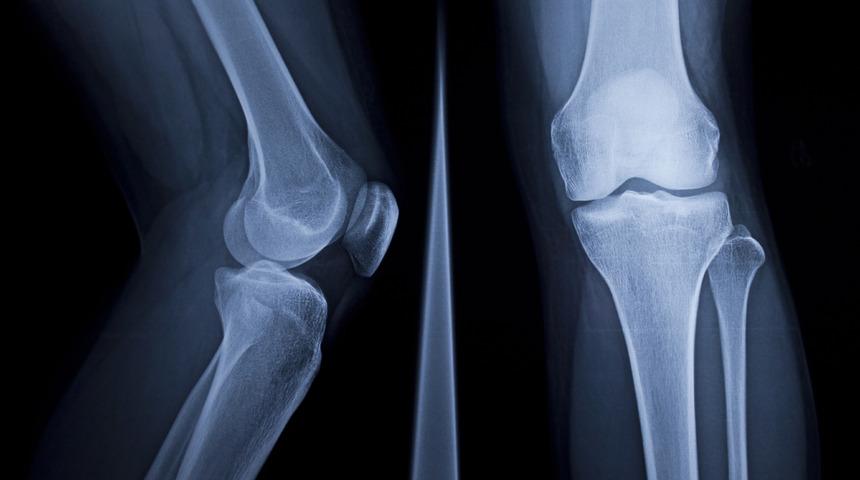

Röntgen ışınları ya da X ışınları, çok kısa dalga boyları, yüksek enerjili olma özellikleri sayesinde tıp alanında kemiklerin görüntülenmesinde kullanılır. Bunun dışında türlü bilimsel alanlarda da kullanılan X ışınları vücut dokularından geçerken kemiklerde soğurulması nedeni ile görüntü oluşmasını sağlar.

Tıp alanında önemli bir noktada olan X ışınları ya da röntgen görüntüleme tekniklerinden biridir. X ışınlarının keşfedilmesine katot ışınları ile crookes tüpü deneyleri büyük oranda zemin hazırlamıştır. Hücrelere zarar verme olasılığı bulunan X ışınları tıbbi kullanımındaki dozlar ve günlük radyasyon seviyelerine oranla daha düşük bir zarar potansiyeline sahiptir. Ayrıca X ışınları güneş gibi kozmik kaynaklardan da yayılabilmektedirler.